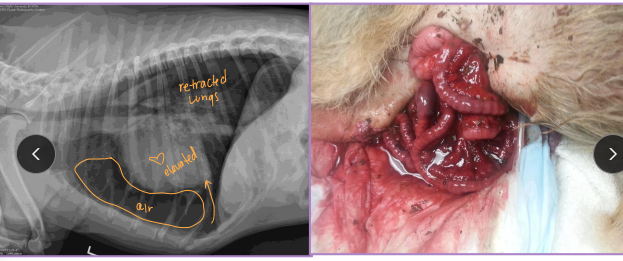

Pelvis Fractures

Considerations: Multi physes, normally breaks at multi sites

Sciatic n.: through ischiatic notch

Weight transfer: paw → tibia → femur → acetabulum → ilium → SI joint

Et: males > females, trama

Dt: Rads, CT for complex fractures/Sx planning

Tx:

Rx: non-displaced, unilateral, non-articular, non-weight-bearing fractures

6 w crate rest, sling, pain control, controlled walks, PT

Sx: ilium/acetabulum/SI joint (weight-bearing), bilateral fractures, displacement, colon compromise, pelvic canal compromise (parturition), sciatic entrapment